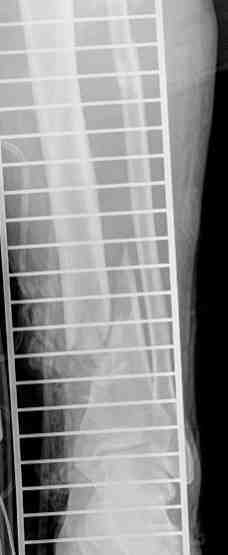

Выше приведены рентгенограммы 13-летнего подростка, страдающего от огнестрельного многооскольчатого перелома дистальной трети бедра. AO наружный фиксатор наложенный в день травмы не дал приемлемой редукции. Через три недели после перелома аппарат Илизарова был наложен без попытки одномоментной репозиции на операционном столе. There are X-Rays of a thirteen year old boy with a comminuted distal femur fracture secondary to a gunshot wound, initially treated with an AO external fixator. The alignment was unacceptable and an Ilizarov external fixator was applied three weeks after the injury. No attempt of definitive reduction was made during the surgery.

Гексаподная приставки наложена на 10 дней и приемлемая редукция была получена. The Hexapod set was applied for ten days and acceptable reduction was received.

По окончанию редукции Гексаподный сет был снят и дальнейшее ведение больного проходило в стандартном режиме аппарата Илизарова. Хороший анатомо-функциональный результат был получен. When reduction was finished, the Hexapod set was removed and further management has been continued by standard Ilizarov regime. Good anatomic and functional results were achieved.